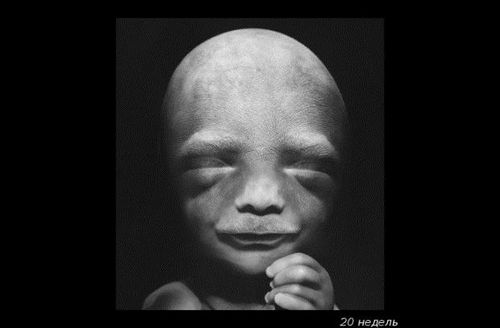

Можна добре розглянути личко малюка. Як думаєте, він схожий на тата? Дитина активно моргає, відкриває ротик і удосконалює хапальний рефлекс.

До 20-му тижні вагітності плід виріс до 25 см, виглядає як великий банан. Плід вже повністю сформований, а його тонка шкіра не настільки прозора.

У цей період відбувається знакова подія - дитина почує свою маму - биття її серця, дихання, голос (його окостенілі слухові кісточки тепер здатні проводити звуки). Малюк смокче пальчик, стає більш енергійним.